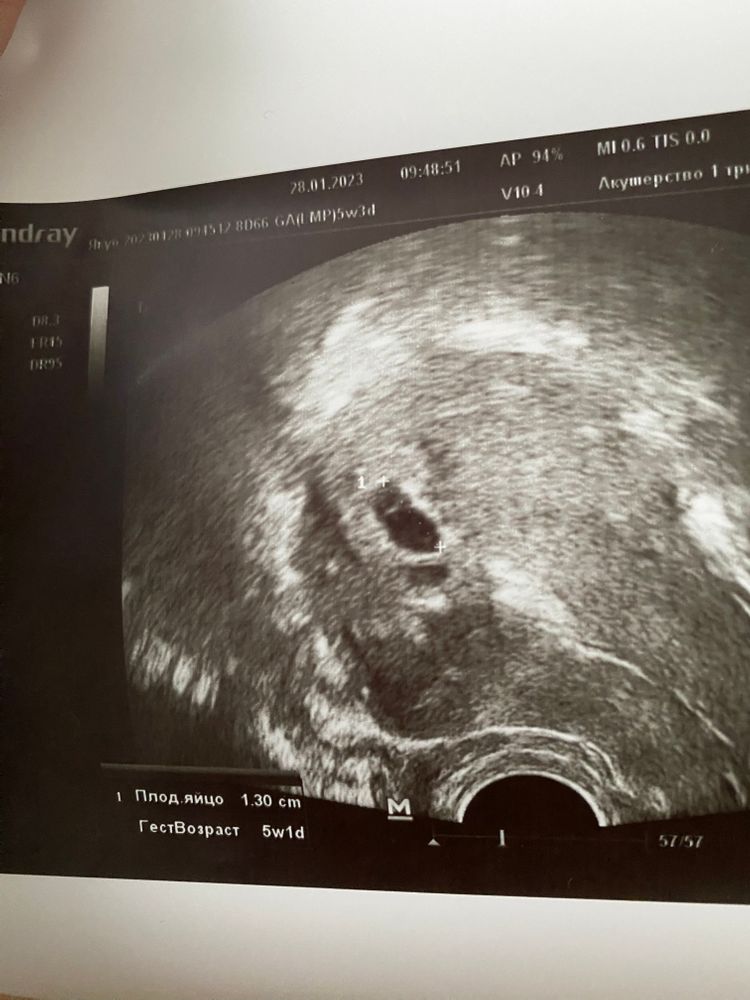

УЗИ, КТГ, доплерС волнением ждала сегодняшний день. Сходила на узи, по последним М срок 5 недель 3 дня. Имеем СВД 13 мм, желточный мешочек 3,3 мм, эмбриона нет.. это еще рано ? При каком свд у Вас было видно эмбриона ?

Еще смутила фраза врача узи «намечается отслойка» и порекомендовала начать пить дюфастон. А мне к врачу в понедельник, думаю там с ней и решим. Как считаете 2 дня же не критично если что ?